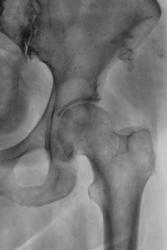

Признаки сужения суставной щели присутствуют. В верхне части головки бедренной кости определяется округлой формы участок просветления, возможно асептический некроз или костная киста.